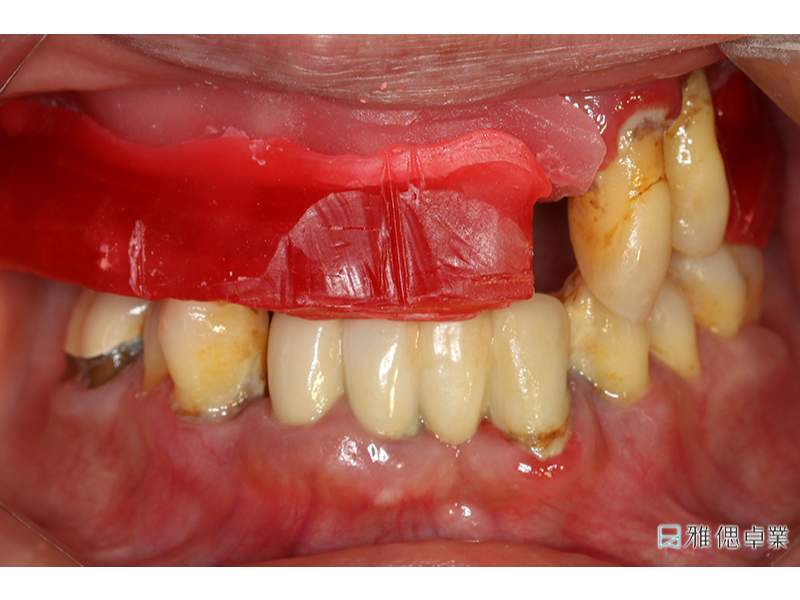

術前環口X光片,上顎只剩下2顆牙齒,下顎也有牙周、排列、咬合等問題

術前